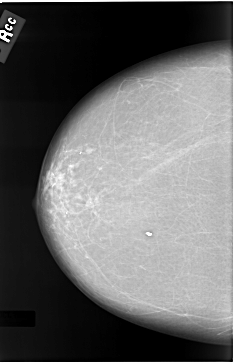

C_0037_1.RIGHT_CC

RIGHT_CC LINES 5824 PIXELS_PER_LINE 3744 BITS_PER_PIXEL 12 RESOLUTION 50 NON_OVERLAY